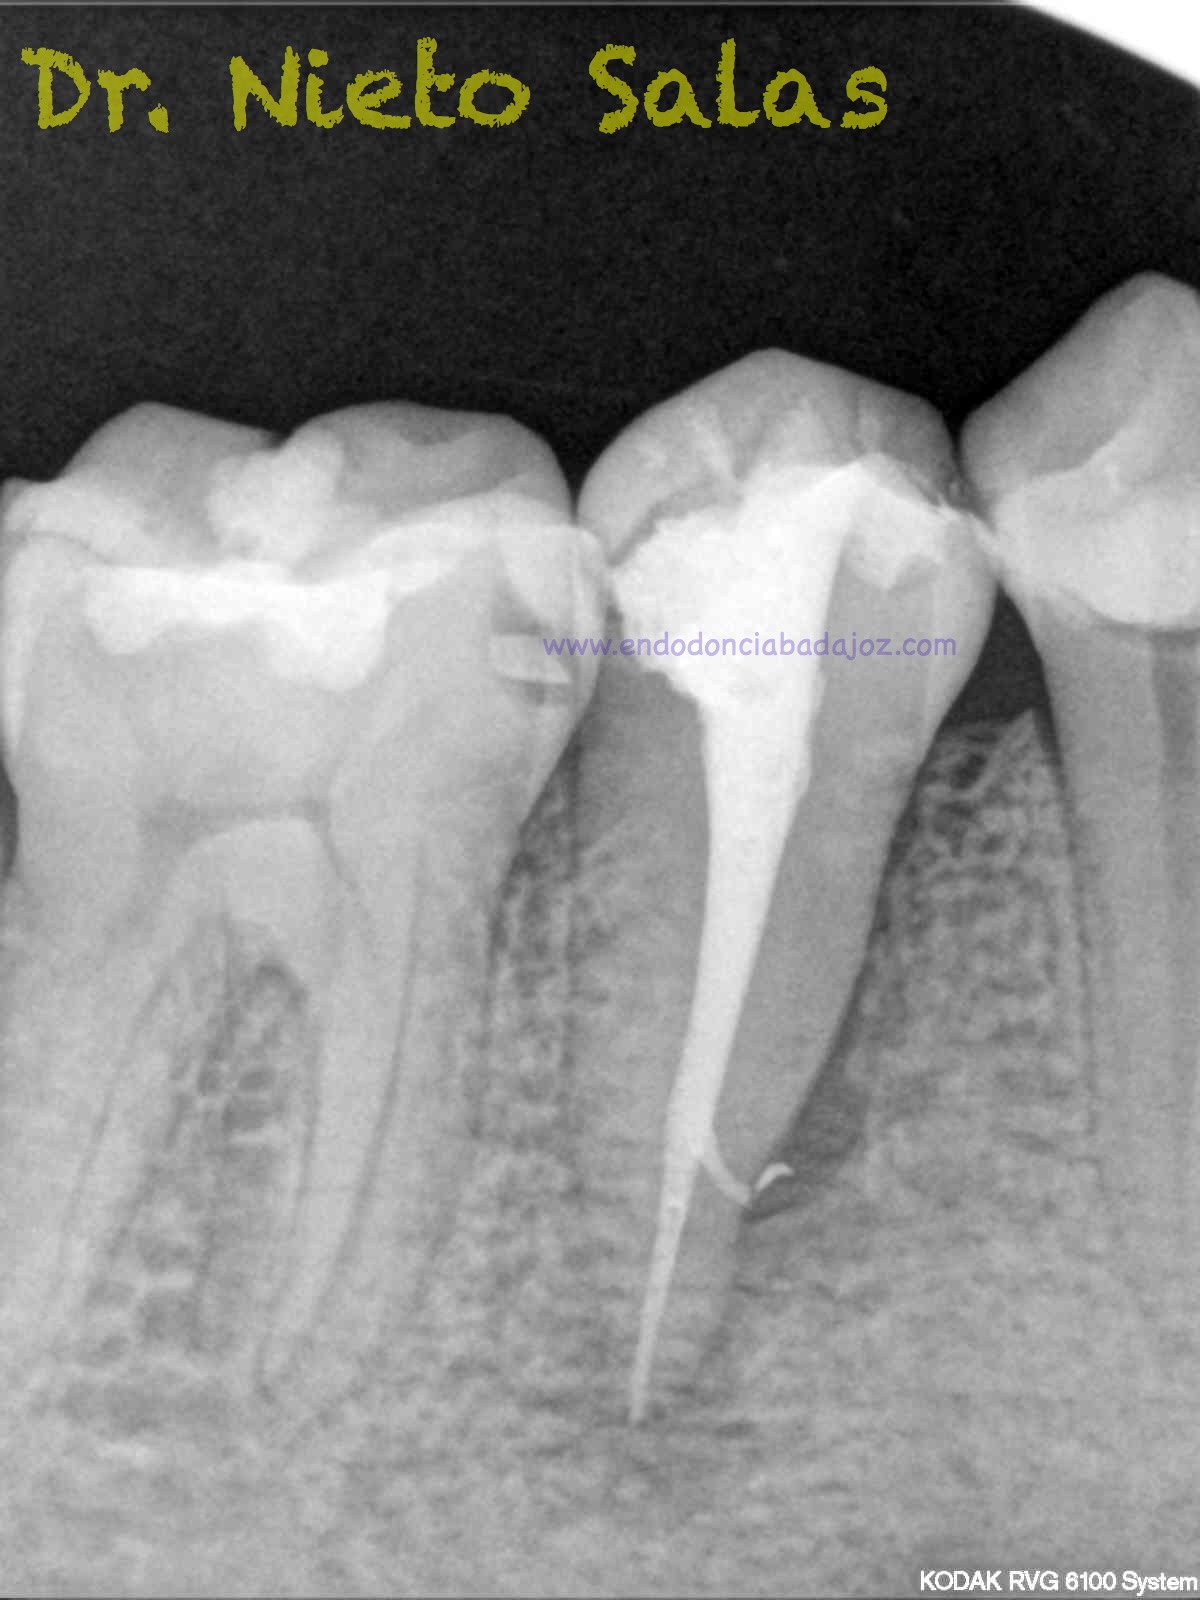

Pero no todo se va a dejar al «poder de la irrigación»,  es muy importante la biomecánica, y la intuición para poder instrumentar esos pequeños conductos laterales que es muchas ocasiones nos dan problemas. Así, pues, os pongo un par de casos que con ayuda de esta «intuición» pudimos hacer un buen tratamiento.

Presentaban un sondaje normal, y sospechamos de que podía tratarse de lesiones por conductos laterales.

Una vez que hemos desbridado biomecánicamente con limas de muy pequeño diámetro, obturamos:

Y este sería el otro caso:

Es muy importante cambiar la proyección de las Rx para tener más información de como hemos sellado el sistema de conductos.